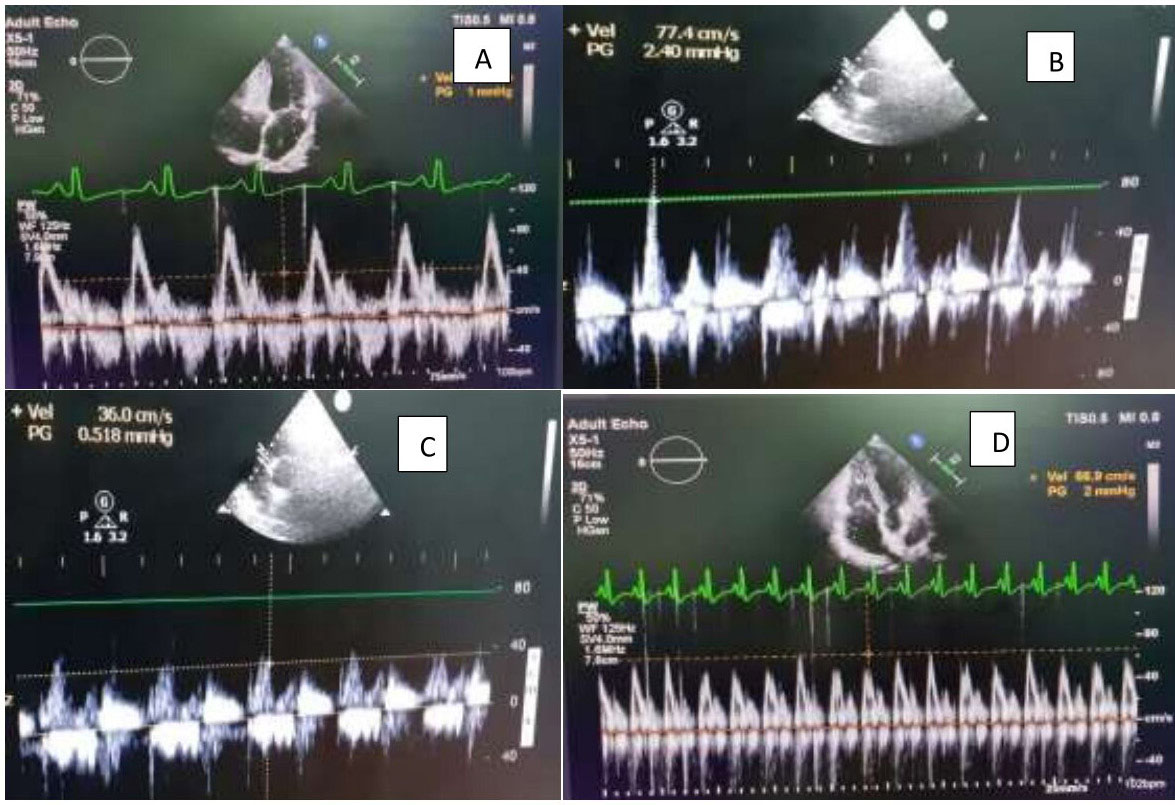

Figure 1. Image of mitral inflow region in a patient showing significant respiratory variation (A,B) pre- operatively as compared to the (C,D) post- operative

In CCP, ventricular filling is severely restricted and occurs only in early diastole with respiratory variation. This underlines the various hemodynamic changes unique to CCP. 15

The doppler echocardiography demonstrates respiratory variation in flow velocity across atrio-ventricular valve to point towards CCP. 16 This is due to the dissociation of intrathoracic and intracardiac pressures and ventricular interdependence.

The various echocardiographic parameters such as IVC congestion, mean LA size, mitral and tricuspid E velocity and TDI findings significantly improved in a study from central India comprising 23 patients of post-pericardiectomy. 17 In our study, there was significant respiro-phasic variation in the mitral and tricuspid E velocity in all patients (P < 0.001). Tissue Doppler imaging (TDI) is a useful for distinguishing CCP from restrictive cardiomyopathy. 18